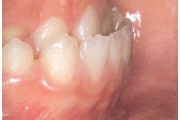

Esimese jäävmolaari ektoopiline lõikumine

) Röntgenülesvõte. Ülemise esimese jäävmolaari lõikumine on takistatud 2. piimamolaari tõttu

Ravijärgne seis. Jäävhammas on täielikult lõikunud.